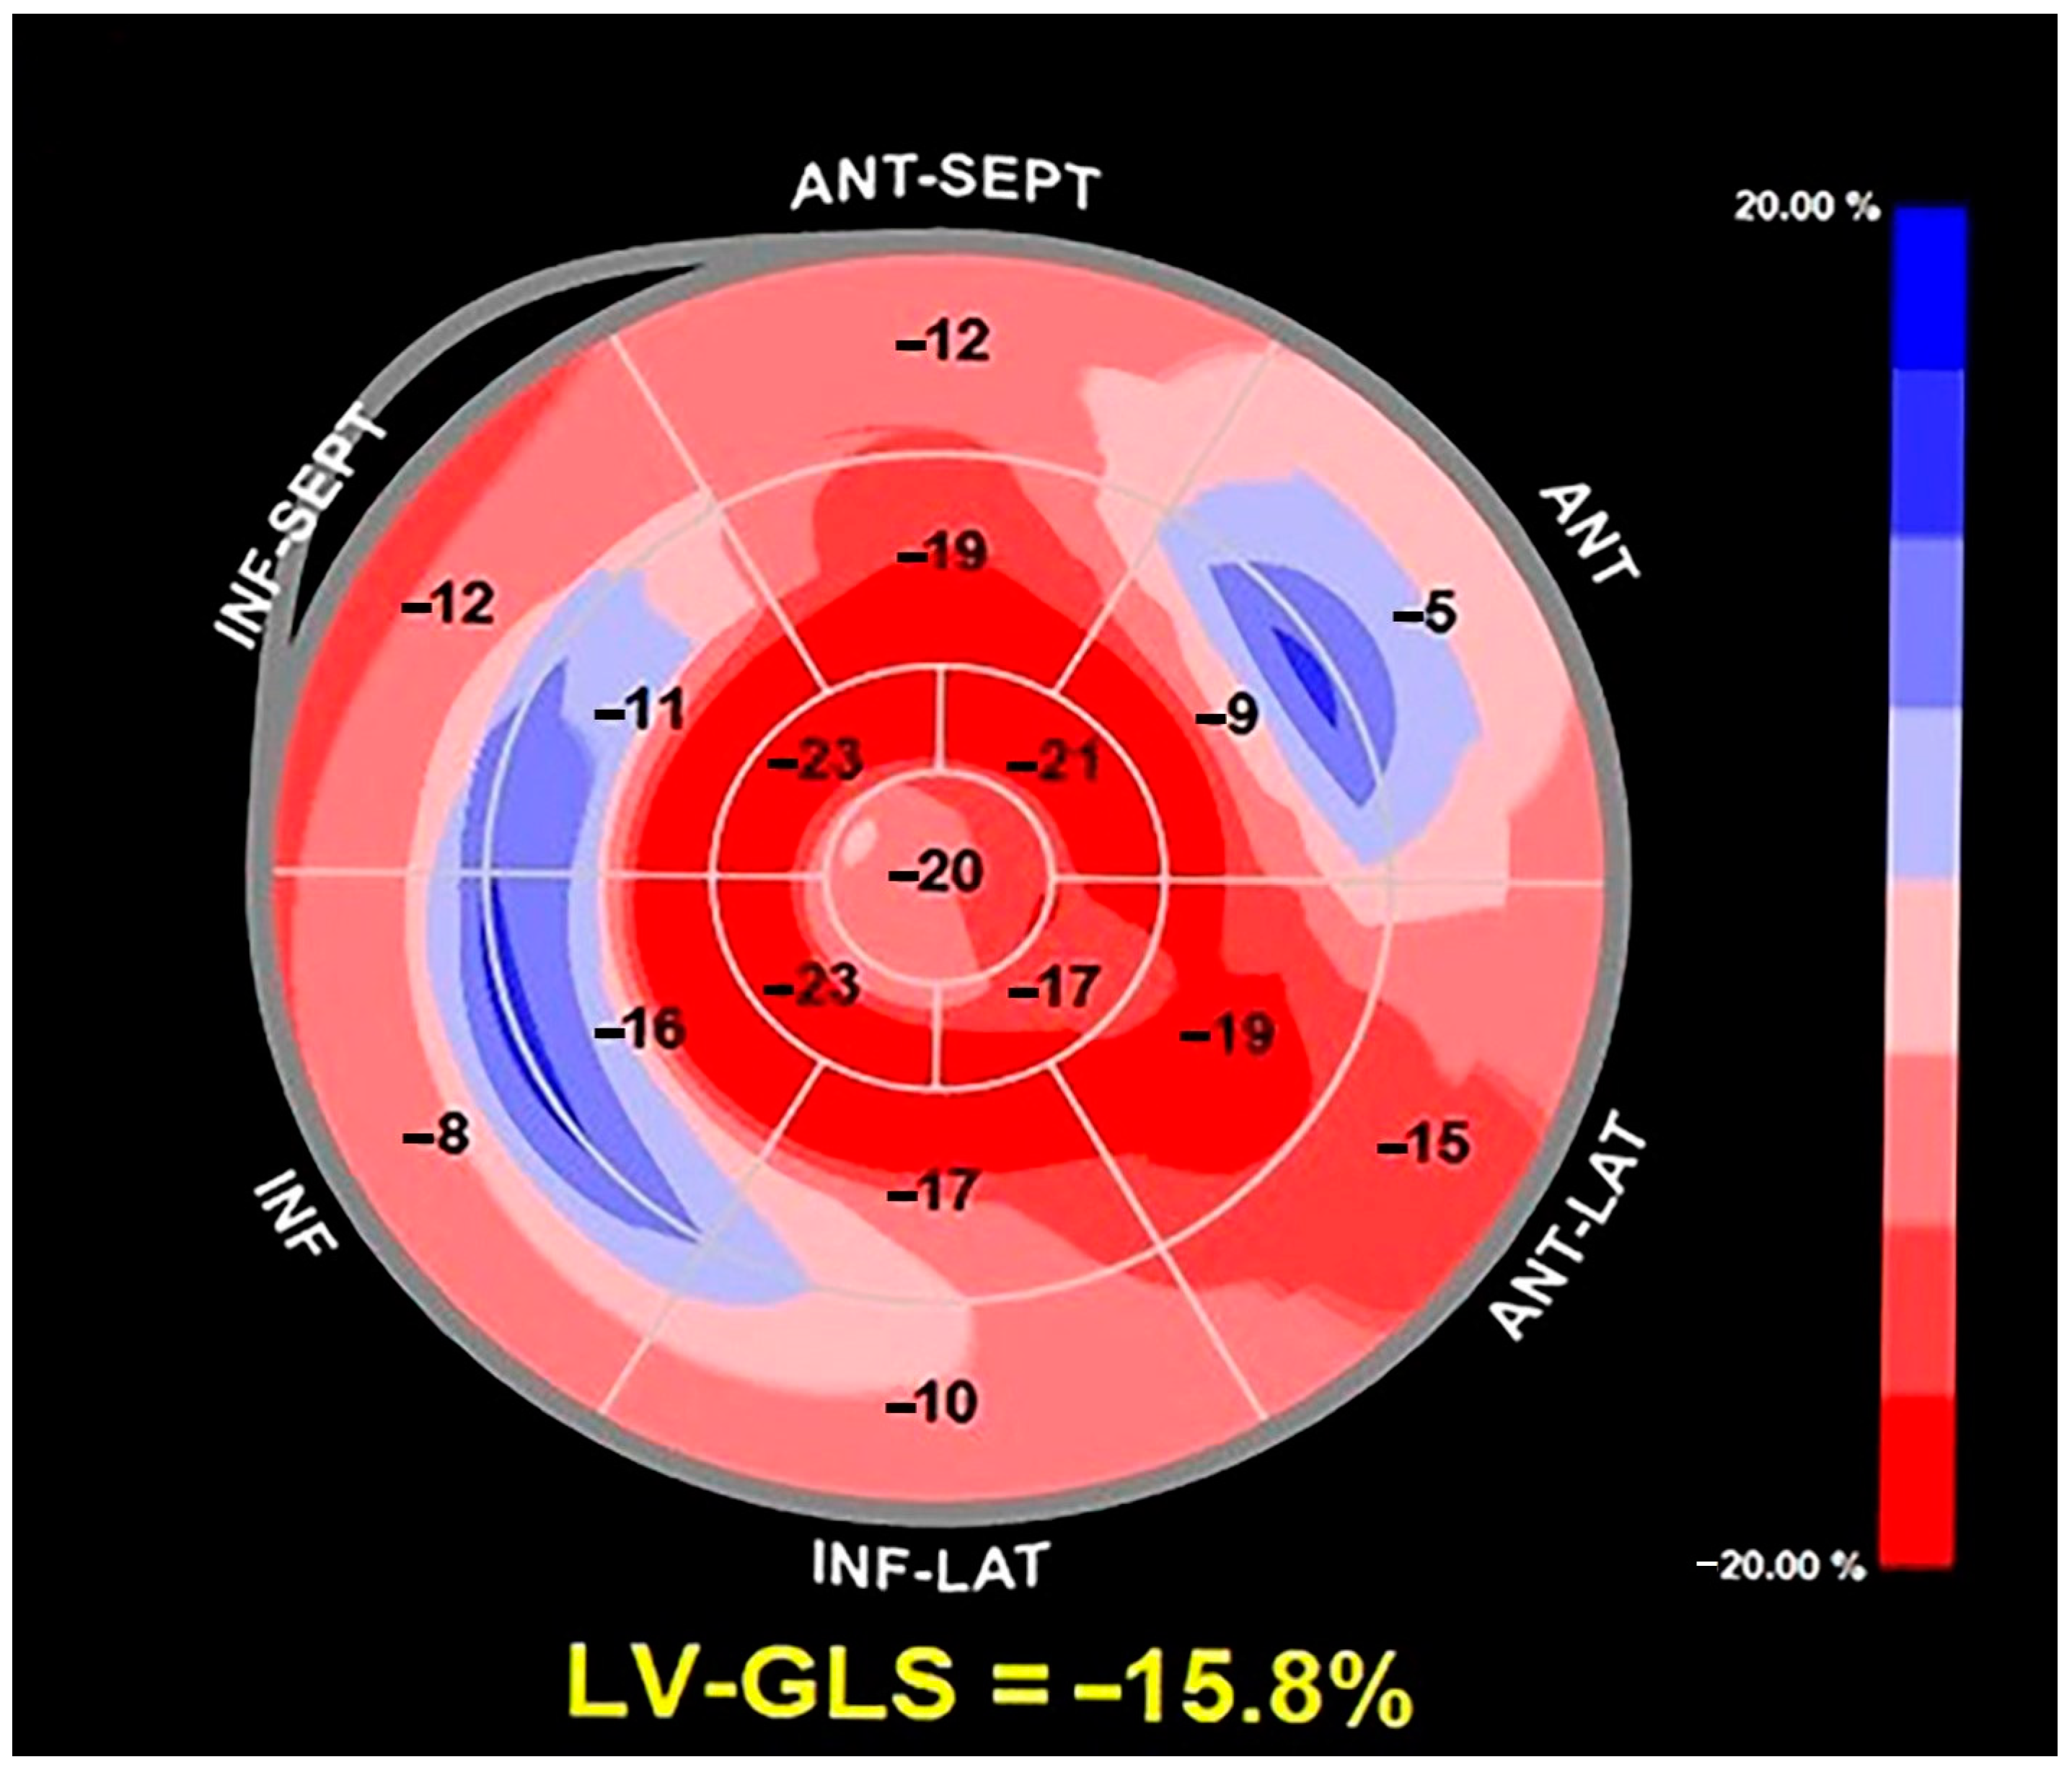

2. Clinical Case

3.2. The Role of Echocardiographic Techniques in MAD Assessment